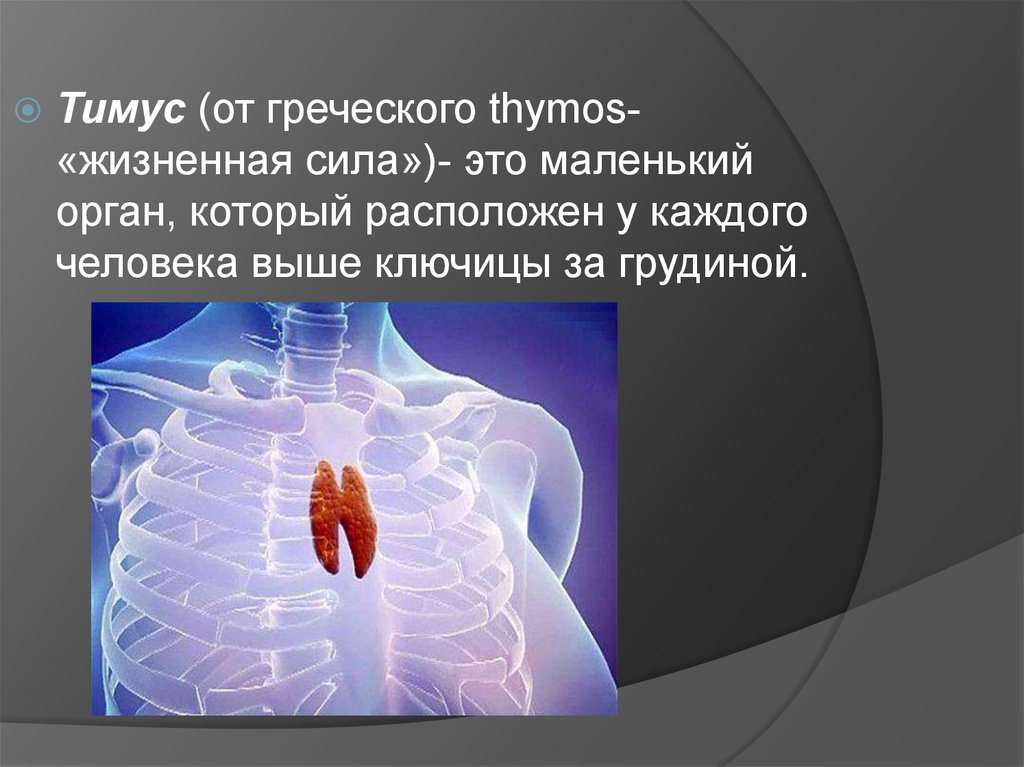

Фотографии вилочковой железы тимуса: структура и функции